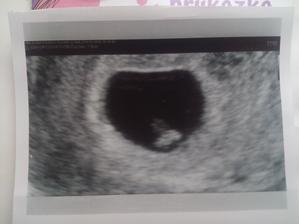

Moje páté miminko na cestě ♥️

Neplánovaně a nečekaně se k nám rozhodlo přijít moje páté miminko ♥️

Doufám a věřím, že bude všechno v pořádku a v září se zdravé narodí 🌞🍀